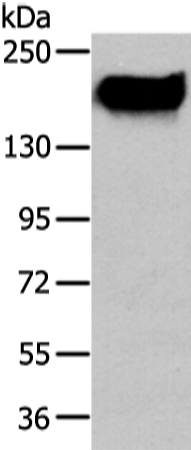

英文名稱: Anti-ABCC1 rabbit polyclonal antibody

抗 原: ABCC1

ABCC1 |

Full name: |

ATP-binding cassette, sub-family C (CFTR/MRP), member 1 |

Synonyms: |

MRP; ABCC; GS-X; MRP1; ABC29 |

SwissProt: |

P33527 |